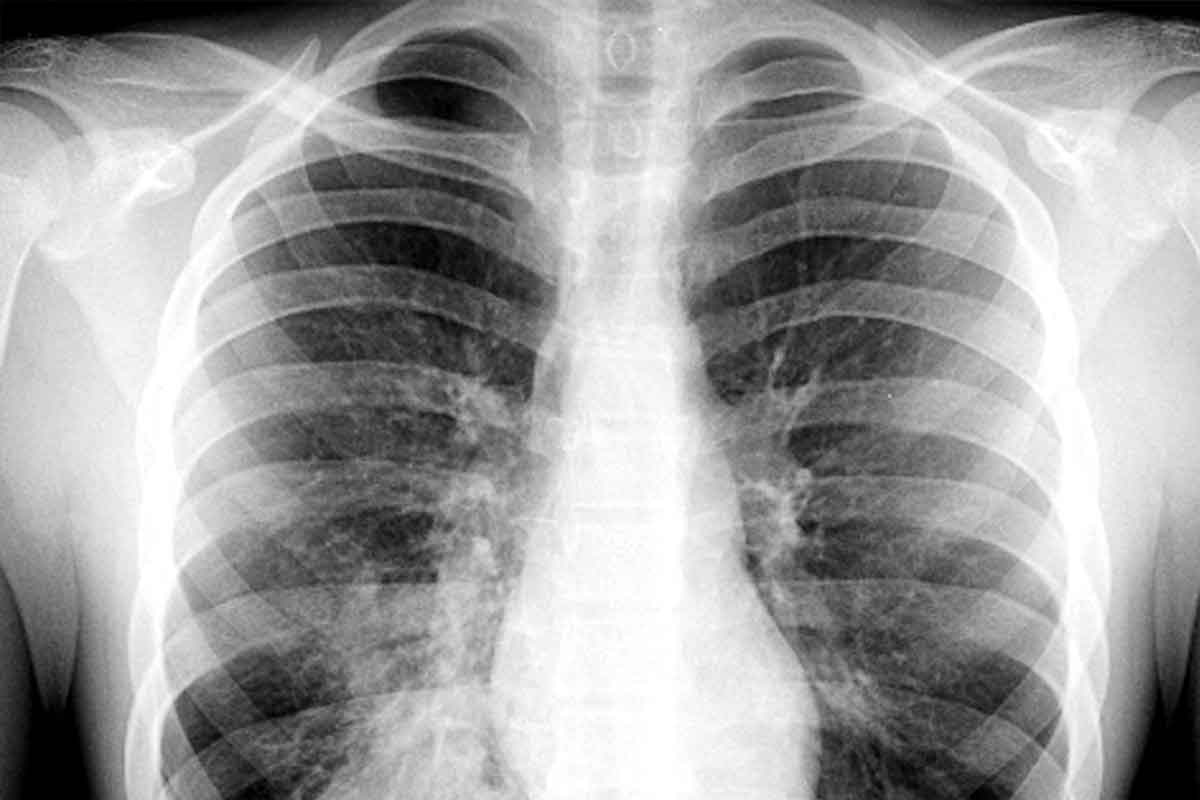

What Pneumonia Does to Your Lungs

Pneumonia causes inflammation in the air sacs of the lungs. This makes it hard for oxygen to get to the bloodstream. People with pneumonia often have a cough, fever, and trouble breathing.

The severity of these symptoms depends on the cause, age, and health of the person. In severe cases, pneumonia can lead to respiratory failure. This is when the lungs can’t get enough oxygen, and it’s very dangerous, mainly for older adults or those with health issues.